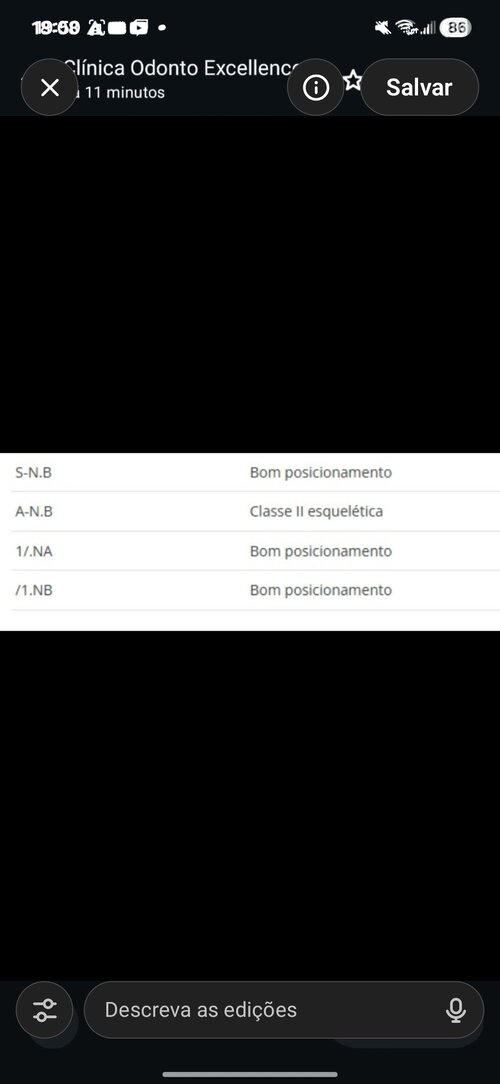

Hi everyone, how are you? I have facial asymmetry — my right side is more drooped/weaker. I won’t drag this out, so I’ll list a few symptoms:

I feel like the right side of my palate is slightly higher, while the left side is slightly lower and wider. I also feel that my lower second molar is a bit inward (when I touch it with my tongue). I probably have bruxism as well — when I open my mouth wide, I notice a difference in my TMJ movement, especially on the right side.

I also feel like my lower teeth are more inward (I’m not sure how to explain it exactly). I’d like to know the best way to fix this. I’ll send some photos and my cephalometric analysis, If you could please use simpler English, I would appreciate it, as I am Brazilian and it's difficult to translate(Note: I also feel a slight muscular difference when touching my face.)

I feel like the right side of my palate is slightly higher, while the left side is slightly lower and wider. I also feel that my lower second molar is a bit inward (when I touch it with my tongue). I probably have bruxism as well — when I open my mouth wide, I notice a difference in my TMJ movement, especially on the right side.

I also feel like my lower teeth are more inward (I’m not sure how to explain it exactly). I’d like to know the best way to fix this. I’ll send some photos and my cephalometric analysis, If you could please use simpler English, I would appreciate it, as I am Brazilian and it's difficult to translate(Note: I also feel a slight muscular difference when touching my face.)

Screenshot_20260403_195001_ChatGPT.jpg193.5 KB · Views: 0

Screenshot_20260403_195001_ChatGPT.jpg193.5 KB · Views: 0 -

Screenshot_20260403_195030_ChatGPT.jpg572.1 KB · Views: 0

Screenshot_20260403_195030_ChatGPT.jpg572.1 KB · Views: 0